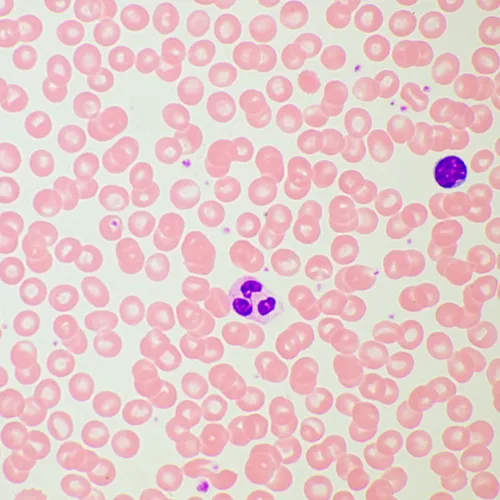

Микроскоп MAGUS Bio 260T – рутинная модель, которая оснащена интеллектуальным освещением, встроенным ЖК-экраном и может дополняться компонентами, которые расширят возможности микроскопа для работы в темном поле, с фазовым контрастом, в люминесцентном свете или с применением поляризации.

В базовой комплектации микроскоп работает в светлом поле с прозрачными и полупрозрачными тонкими биологическими препаратами. Может применяться в лабораториях и научных учреждениях для рутинных исследований, для обучения молодых специалистов.

- В базовой комплектации микроскоп предназначен для исследования биологических образцов в светлом поле в проходящем свете